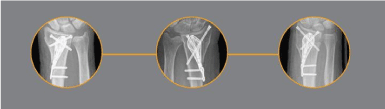

Figure 2. Fracture of the distal radius with the crushing of the metaphyseal bone. Reopening of the fracture site. The aim is to maintain it open

Figure 3. The reduction of the fracture opens the compaction chamber which collapse is opposed by the elastic reaction of the nail. The self-stability is ensured by an "S" design with 3 fix points

Figure 4. Moment of the compressive force exerted on the locking screw of the nail and the palmar plate